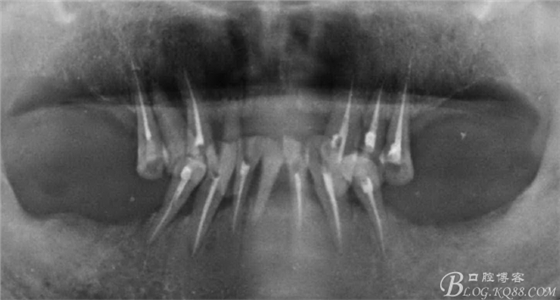

病人上前牙缺失,下頜前牙伸長(zhǎng)已經(jīng)咬到上頜牙槽脊,看x線片

牙槽骨嚴(yán)重吸收,全口牙還剩下21顆牙,但是 在1度松動(dòng)的牙齒只有12顆牙,其它牙都在2度到3度松動(dòng)之間

上頜--15、13、23、24、25

下頜--44、43、42、41、32、33、34